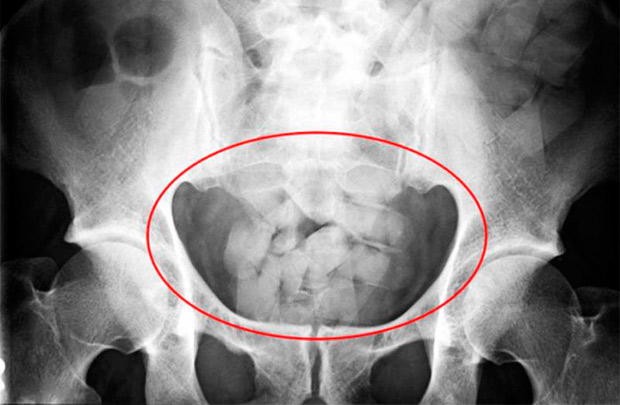

По словам следователя, оперативная информация подтвердились. Посредством нехитрой манипуляции — промывания желудка — сверток фольги был извлечен из организма задержанного. В фольге находился небольшой кусочек смолообразной смеси.

— Проведенная экспертиза показала, что вещество, весом 0,27 г, является наркотическим, известным под названием «гашиш», — продолжает Ольга Русакова.